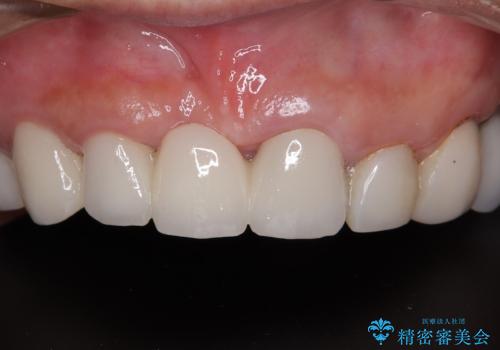

[ 歯周病・矯正・セラミック補綴 ] 歯の総合的なマネージメントを行う包括的歯科治療の実践

![[ 歯周病・矯正・セラミック補綴 ] 歯の総合的なマネージメントを行う包括的歯科治療の実践の症例 治療前](https://seimitsushinbi.jp/wp/wp-content/uploads/2025/10/7db12d5413070a950bc6275b957b7f9f-500x350.jpg?v=1760767674)

![[ 歯周病・矯正・セラミック補綴 ] 歯の総合的なマネージメントを行う包括的歯科治療の実践の症例 治療後](https://seimitsushinbi.jp/wp/wp-content/uploads/2025/10/eaeb8f32e6e2496b4cca2d55d85ba36c-500x350.jpg?v=1760768149)